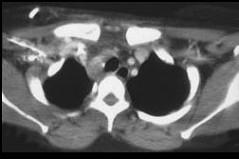

男,33岁,车祸后十余天,请结合影像学检查,选出最可能的诊断 ( )A、淋巴瘤B、纵隔血肿C、胸内甲状腺肿D、胸腺瘤E、纵隔畸胎瘤

问题 男,33岁,车祸后十余天,请结合影像学检查,选出最可能的诊断 ( )

选项 A、淋巴瘤 B、纵隔血肿 C、胸内甲状腺肿 D、胸腺瘤 E、纵隔畸胎瘤

答案 B